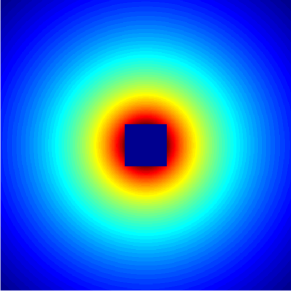

Compressed Sensing (CS) provides a theoretical framework to justify the downsampling of -space (2D or 3D Fourier domain) in Magnetic Resonance Imaging (MRI). CS-MRI is usually based on independent random drawing of -space locations according to a prescribed density. From recent theoretical works [3, 4], one can derive an optimal sampling density that reduces at most the number of samples collected in MRI without degrading the image quality at the reconstruction step [5, 6]. In [7], simulations show that distributions with radial decay (see Fig. 1(a)) with full -space center acquisition perform better in numerical experiments.

However, such sampling schemes are not performed along continuous lines and thus not physically plausible in MRI because of the constraints involved on the magnetic field gradient (magnitude and slew-rate). In [8], we have proposed a new approach to design continuous sampling trajectories based on the solution of Travelling Salesman Problem (TSP), as illustrated in Fig. 1(b). The specificity of this approach is that the empirical distribution of the trajectory can approximate any prescribed distribution . Such a curve is called a -Variable Density Sampler (-VDS). Unfortunately, continuity of the sampling trajectory is not a sufficient condition in MRI and it is not clear how to design admissible gradient waveforms to traverse such a trajectory.

| (a) | (b) |

|---|---|

|

|